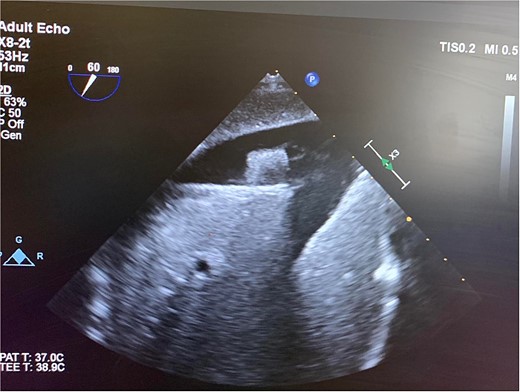

In the OR, exploratory laparotomy, right nephrectomy, liver packing, and pericardial window were performed. The pericardial window was negative for blood. With no suspected cardiac injury, intraoperative fluoroscopy (Fig. 1) and transesophageal echocardiogram (TEE) (Fig. 2) were used to locate the bullet. It was suspected to be intravascular secondary to venous embolism from the retro-hepatic inferior vena cava (IVC). Cardiothoracic surgery was consulted for removal of the bullet. With abdominal hemorrhage controlled, the surgeons agreed the patient was an acceptable risk for anticoagulation and cardiopulmonary bypass. Sternotomy was performed, the patient was placed on cardiopulmonary bypass, and the bullet was removed through a right atriotomy.

Intraoperative TEE demonstrating the intravascular bullet in the IVC.